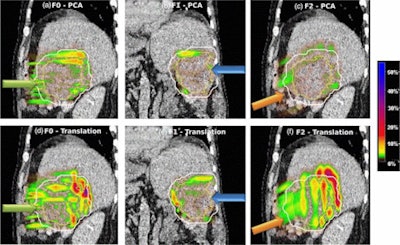

Absolute dose difference of 4D dose distributions considering ground truth motion versus reconstructed motion from either the PCA model (top) or the 2D translation model (bottom) prediction for three fields (the arrows indicate the field direction). All images courtesy of Ye Zhang.

Absolute dose difference of 4D dose distributions considering ground truth motion versus reconstructed motion from either the PCA model (top) or the 2D translation model (bottom) prediction for three fields (the arrows indicate the field direction). All images courtesy of Ye Zhang.At the PSI, the newest proton therapy gantry (Gantry2) is equipped with a beam's eye view (BEV) imaging system that can acquire 2D x-ray fluoroscopy images during proton therapy. But what's really needed is information regarding the 3D deformable motion throughout the whole target region. To achieve this, the PSI team has proposed a method for extracting 3D motion from surrogate motion detected using the BEV system (Physics in Medicine and Biology, 2013 November 21, Vol. 58:24, pp. 8621-8645).

To further investigate the feasibility of motion tracking for scanned proton beam therapy, the PSI team examined the effect of motion prediction errors on the resulting 4D dose distributions. For all subjects, they calculated 4D dose distributions (for a single field and using Gantry2's scanning parameters) using both the ground-truth motion and predicted motion. Predictions were performed using both the PCA model, where full 3D motion is reconstructed, and a translation model, in which every point in the liver is assigned the same motion vector of the fiducials.

Comparing absolute dose differences between ground truth-based and prediction-based plans (using fiducial markers) showed that motion predictions from the translation-only scenario were poor, with maximum dose differences of more than 50%. Plans based on PCA-predicted motion, on the other hand, were similar to those based on ground-truth motion. Here, absolute dose differences of more than 5% occurred in only 3.61% (median) or 15.13% (maximum) of dose calculation points in the irradiated volume. Similar results were seen when tracking diaphragm motion.